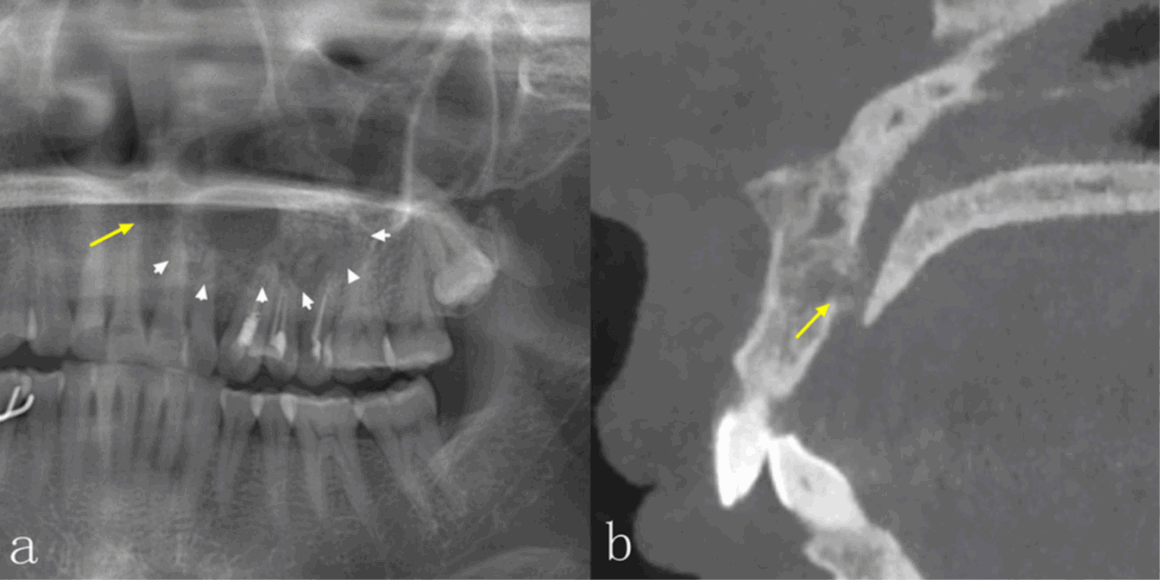

No obstante, la TCCB también tiene sus desventajas. Por ejemplo, la TCCB es propensa a diversos artefactos, especialmente artefactos metálicos y de movimiento, que pueden tener un efecto perjudicial sobre la calidad de la imagen. En comparación con la tomografía computarizada espiral (tomografía medica), su resolución de contraste es menor y los tejidos blandos se visualizan con menor calidad. La dosis de radiación y el coste son también factores importantes que deben tenerse en cuenta a la hora de tomar decisiones clínicas. La dosis depende principalmente del tipo de equipo y de los ajustes de exposición, incluyendo el campo de visión, el tiempo de exposición, la corriente del tubo (mA) y la energía/potencial (kV).6 En comparación con la PAN, la dosis efectiva de radiación de la TCCB suele ser significativamente mayor, lo que debe tenerse en cuenta cuando se requiere la obtención de imágenes. Las diferencias significativas en el aspecto radiológico de las lesiones intraóseas entre la PAN y la TCCB se encuentran en la integridad de los bordes corticales, la expansión de los límites anatómicos circundantes, el adelgazamiento cortical, la destrucción cortical y la reabsorción radicular, especialmente en las regiones anteriores de ambos maxilares y en el maxilar superior. La TCCB también mejora la precisión diagnóstica, especialmente en las lesiones del maxilar superior.

La TCCB proporciona información más completa y detallada, lo que resulta útil para realizar el diagnóstico. Aunque la precisión diagnóstica estaba estrechamente relacionada con la experiencia de los médicos, la discrepancia entre los dos estudios se atribuye muy probablemente al mayor tamaño de la muestra de nuestro estudio. La TCCB fue precisa a la hora de mostrar las características de las lesiones, como la ubicación, la localización, la densidad interna, la expansión y su efecto sobre las estructuras circundantes, lo cual es de ayuda a los odontólogos a realizar un diagnóstico más preciso.